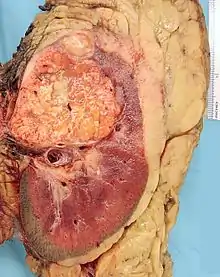

Histopathology

The gross and microscopic appearance of renal cell carcinomas is highly variable. The renal cell carcinoma may present reddened areas where blood vessels have bled, and cysts containing watery fluids.[58] The body of the tumour shows large blood vessels that have walls composed of cancerous cells. Gross examination often shows a yellowish, multilobulated tumor in the renal cortex, which frequently contains zones of necrosis, haemorrhage and scarring. In a microscopic context, there are four major histologic subtypes of renal cell cancer: clear cell (conventional RCC, 75%), papillary (15%), chromophobic (5%), and collecting duct (2%). Sarcomatoid changes (morphology and patterns of IHC that mimic sarcoma, spindle cells) can be observed within any RCC subtype and are associated with more aggressive clinical course and worse prognosis. Under light microscopy, these tumour cells can exhibit papillae, tubules or nests, and are quite large, atypical, and polygonal.

The recommended treatment for renal cell cancer may be nephrectomy or partial nephrectomy, surgical removal of all or part of the kidney.[3] This may include some of the surrounding organs or tissues or lymph nodes. If cancer is only in the kidneys, which is about 60% of cases, it can be cured roughly 90% of the time with surgery.